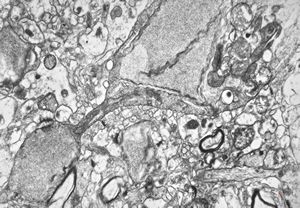

F,49y. | purulent meningitis- meningococcal v.s.